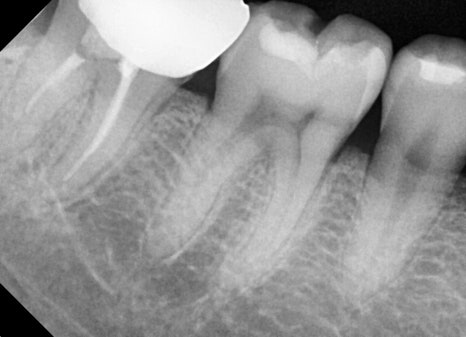

파노라마 엑스레이 촬영을 통해

오른쪽 아래 첫 번째 어금니(제1대구치)에 깊은

충치가 진행되어 있는 상태를 확인했습니다.

다행히도 신경까지는 도달하지 않아 신경치료 없이

인레이 치료로 치아를 살릴 수 있는 상태였습니다.